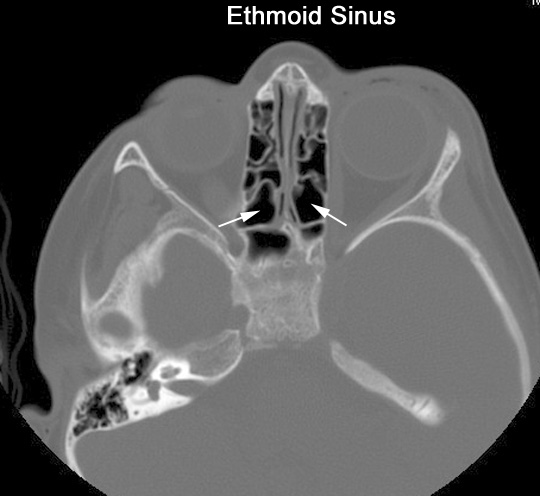

Identify the ethmoid sinus. Click the image for labeling.